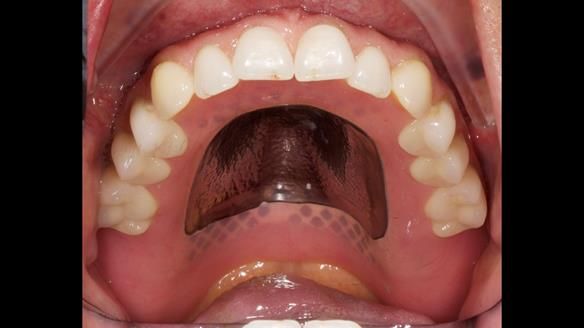

Provision of metal reinforced complete dentures. The lower can be converted to implant support in the future, if needed.

Following consultation, the patient chose to have replacement upper and lower conventional metal reinforced dentures made (professional fee £7,978 GBP). Metal reinforcement was given because of a history of breaking dentures. The lower denture was designed to allow conversion to an implant supported over denture if required (additional fee £12,542 GBP).

The clinical situation and treatment process is shown in detail below with photographs. I (Finlay Sutton) provided the clinical work and Rowan Garstang provided the technical work.